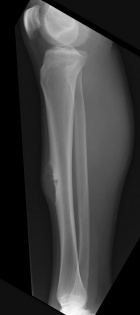

21 year old male with increasing leg pain and enlarging mass for three years